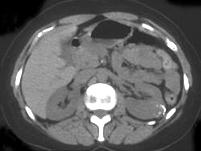

问题 女,24岁,请根据所示图像,选择最可能诊断 ( )

选项 A、左侧囊性肾癌 B、左侧肾盂旁囊肿 C、左侧钙化性肾囊肿 D、左侧肾包虫囊肿 E、左侧单纯性肾囊肿

答案 C